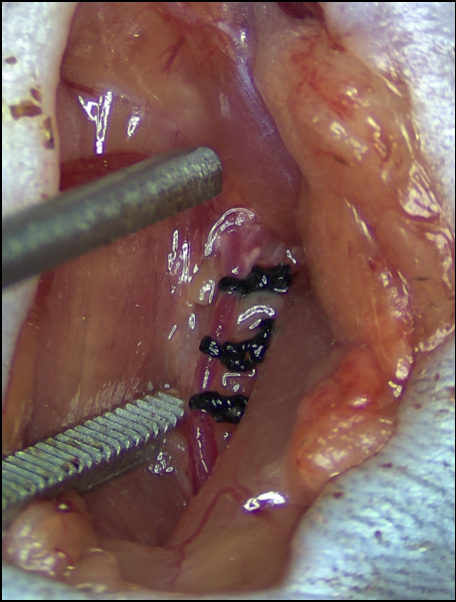

研究团队成功建立了慢性颈动脉闭塞(CCAO)小鼠模型。

难点: 需要区分急性和慢性过程,避免急性血栓导致的大面积脑梗死(这会直接致死或造成明显神经功能缺损)。

结果: 术后1周表现为狭窄,术后1个月实现完全闭塞,且小鼠未出现急性卒中表现,模拟了人类的“无症状”慢性病程。

图:小鼠CCAO模型建立